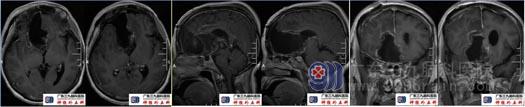

术后复查头颅MRI示原病灶已大部分切除,幕上梗阻性脑积水并室周间质性水肿较前减轻。